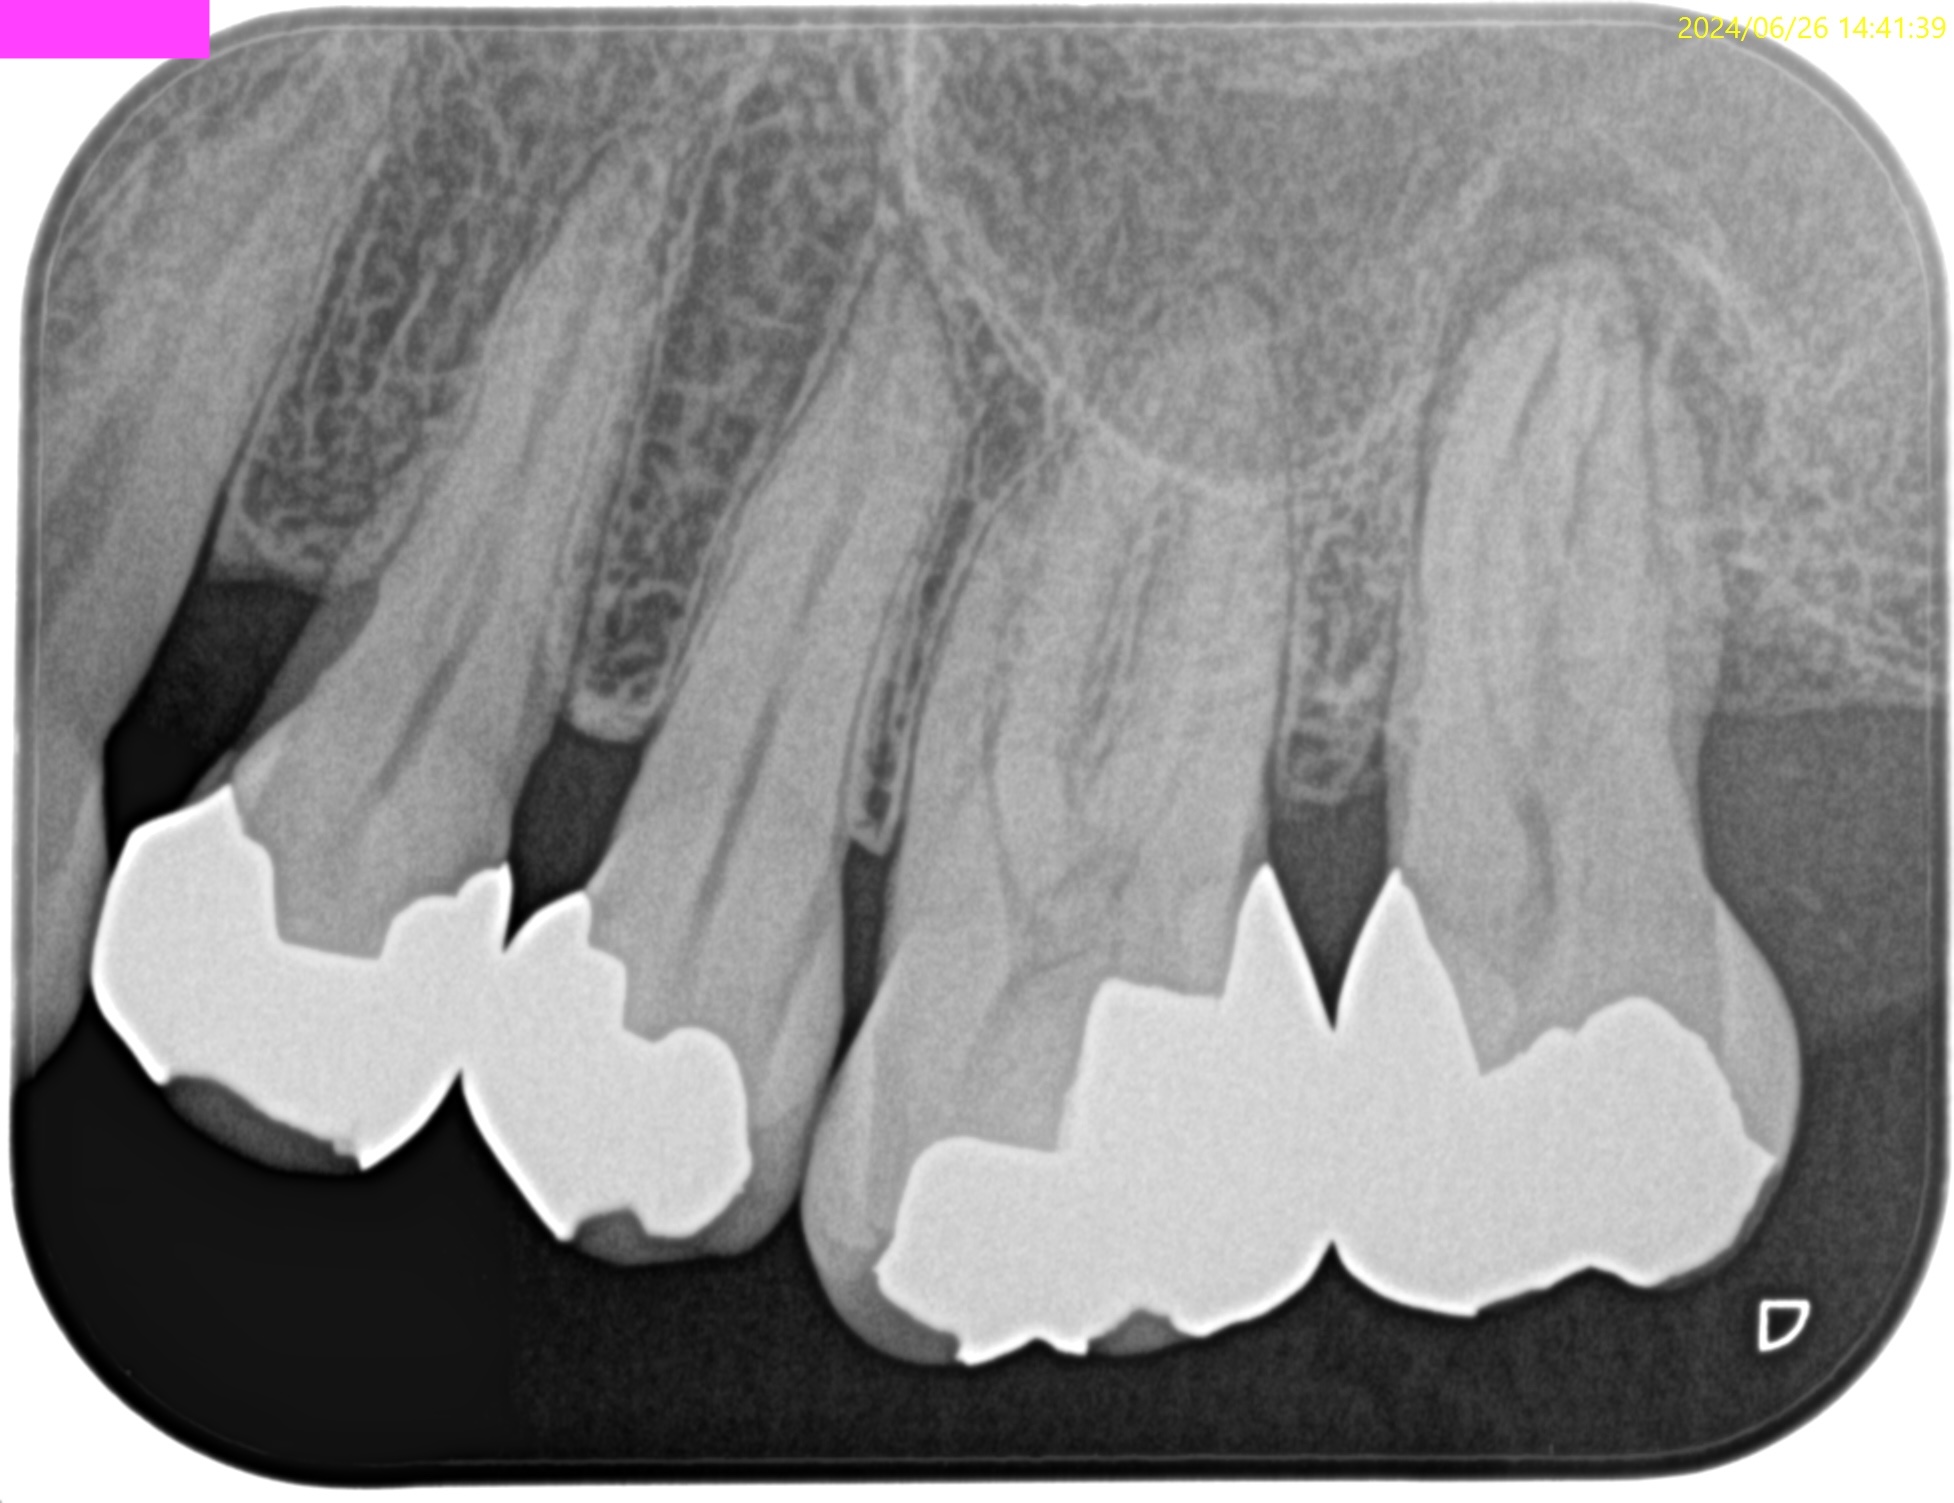

PA(2024.7.31)

CBCT(2024.7.31)

根尖病変があり、上顎洞炎を呈している。

根管治療が必要だ。